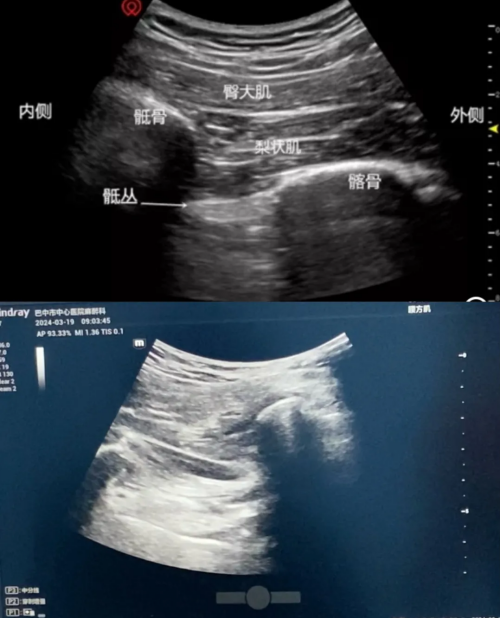

手术当天,患者入手术室后进行完善的监护、保温,胡了凡在超声引导下对患者实施了高位髂筋膜阻滞,待麻醉起效后再让患者处于侧卧位实施超声引导下的骶丛神经阻滞,手术开始半个小时前使用右美托咪定进行充分镇静,以减轻患者的恐惧感。术中,患者生命体征平稳,手术顺利完成。

神经阻滞麻醉是在超声引导下将局麻药注射到支配手术部位的神经周围,暂时阻断神经的传导功能,从而达到良好的麻醉镇痛效果。这种区域麻醉的方法能实现局限于手术部位麻醉的效果,而对全身的生理影响极小,血流动力学的波动微乎其微,对高龄、基础疾病较多的患者尤为适用。(黄联学)